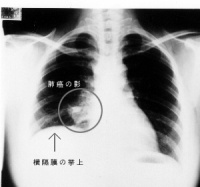

肺部常见的疾病有:气胸、肺大泡、肺气肿、肺部阴影(严格讲不算单独疾病,但临床上常作为多种肺部占位病变的统称)和肺癌等。